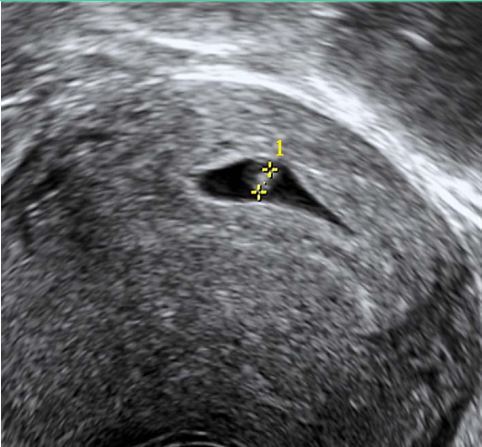

2.超声检查 妊娠早期超声检查的主要目的是确定宫内妊娠,排除异位妊娠和滋养细胞疾病,估计孕龄,排除盆腔肿块或子宫异常;若为多胎,可根据胚囊的数目和形体判断绒毛膜性(图5-1)。停经35日时,宫腔内见到圆形或椭圆形妊娠囊(gestational sac,GS);妊娠6周时,可见到胚芽和原始心管搏动。停经14周,测量胎儿头臀长度(crown-rump length,CRL)能较准确地估计孕周,矫正预产期。停经9~14周B型超声检查可以排除严重的胎儿畸形,如无脑儿。B型超声测量指标有胎儿颈项透明层(nuchal translucency,NT)和胎儿鼻骨(nose bone)等,可作为孕早期染色体疾病筛查的指标。彩色多普勒超声可见胎儿心脏区彩色血流,可以确诊为早期妊娠、活胎。

图5-1 早孕期B型超声图像

妊娠7周见妊娠囊 妊娠8周1天测量头臀长度